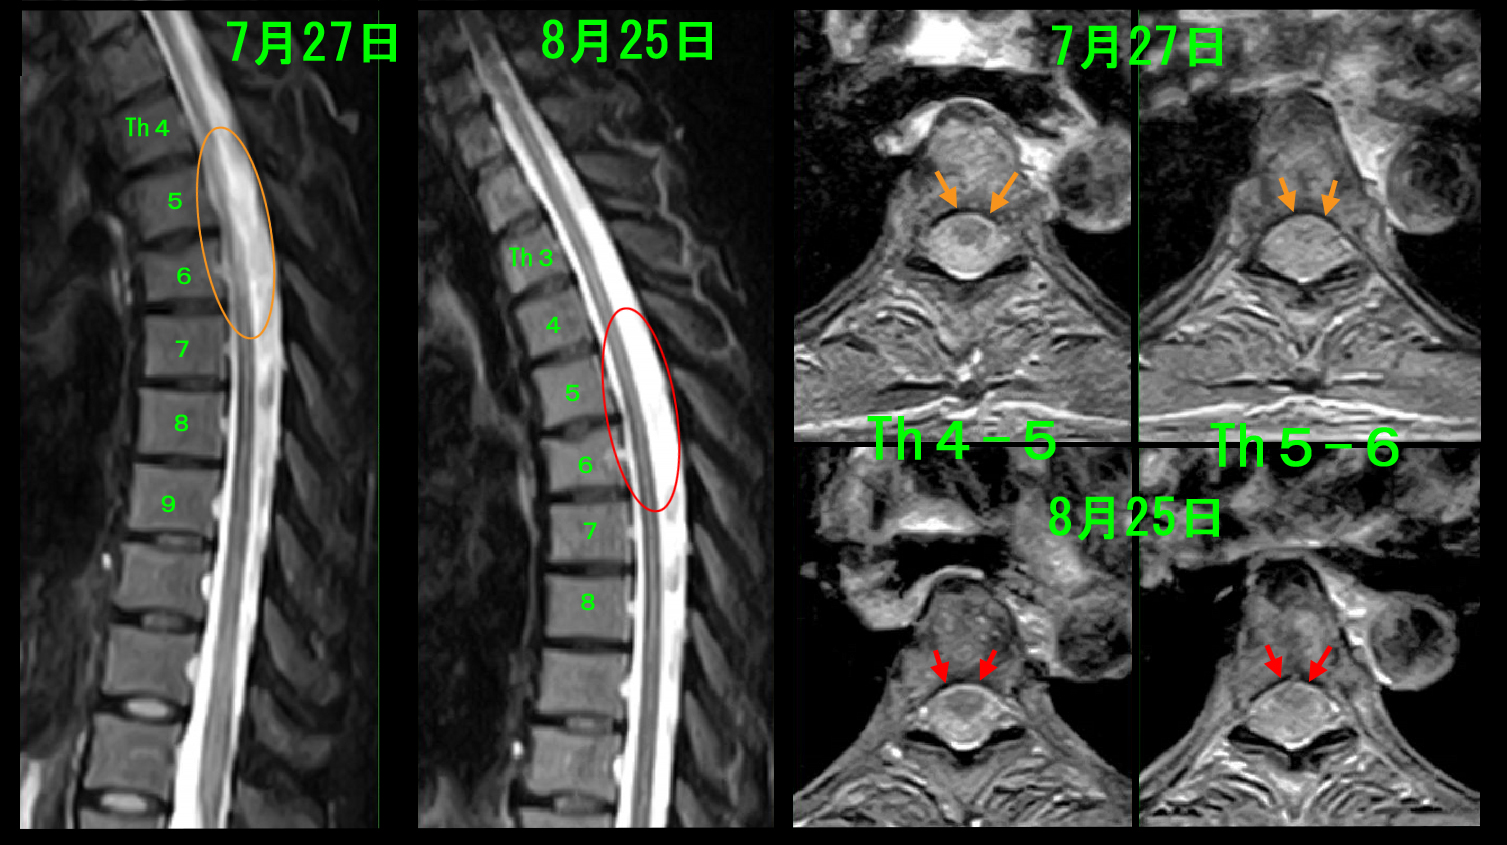

頚椎に異常が確認されなかったため、続けて胸椎のMRI検査を行いましたが、はオレンジ丸領域の脊髄が明瞭に描出されていないと評価しました。脊椎の後ろに脊髄がありますが、縦に走る黒い部分が脊髄で、脊髄は硬膜という袋に入っていて、硬膜の中を髄液という水が流れています。縦縞のストライプで白い部分が髄液となります。

MRDW.jpg

脊髄を横に切った画像が右側に並ぶ4断面となりますが、脊髄は目玉のように見えるのですが、Th5-6高位では黒目と白目が描出されていません。私はこれを脊髄が浮腫を起こした(腫れた)状態と理解していて、この脊髄の浮腫が背中の苦しさの原因と推察しました。

8月25日に胸椎MRI検査を再検査しました。

MR経過.jpg

Th5-6高位で脊髄の浮腫と評価したぼやけた白黒のストライプも明瞭となり、脊髄の目玉の模様は一応黒目が確認される状態に改善したと評価できます。

追突事故のダメージで胸椎レベルでの脊髄の浮腫が発生し、背中の苦しさの原因となったと理解され、当院の診断と対応により順調に経過した症例でした。